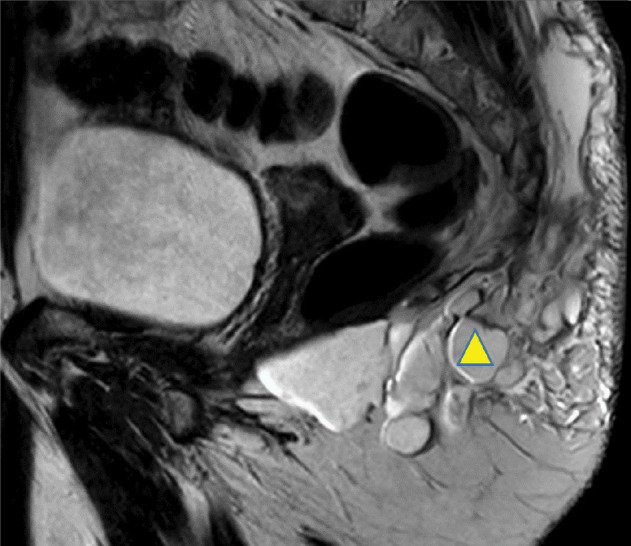

Teaching point: To highlight the potential complications associated with AQUAfilling injections, emphasizing the importance of early detection and proper management.

Abstract Image